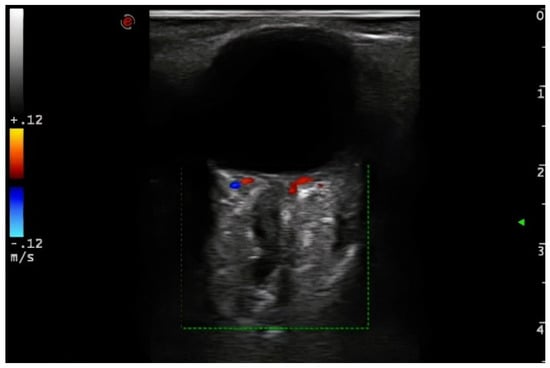

Demographic variables and vascular risk factors were collected. Orbital ultrasound findings were obtained using a 3–9 MHz linear probe (Esaote MyLab70 and My Lab9, Esaote, Milan): the absence of color and pulsed Doppler signal in the peripapillary portion of the CRA (diagnosis of CRAO) (Figure 1) and the presence of hyperechoic material in the retrobulbar circulation of the optic nerve (spot sign) were explored (Figure 2).

Figure 2. Hyperechoic material in the retrobulbar circulation of the optic nerve (spot sign). Note the abscense of color code flow signal in the peripapillar segment of the CRA. 3–9 MHz linear probe (Esaote MyLab70 and My Lab9, Esaote, Milan).